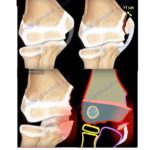

Patellar sleeve fractures

DEFINITION Patellar sleeve fractures are rare injuries occurring in the skeletally immature population( 8 – 12 years) . Characterized by the separation of the cartilage “sleeve” from the ossified patella. Displaced bone-forming tissue will continue to grow and ossify, enlarging, and possibly duplicating the patella. Epidemiology 1% of all fractures in pediatric population Accounts for […]